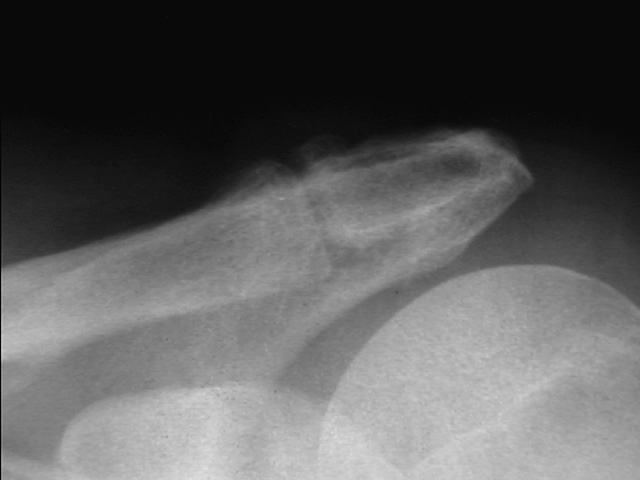

To provide an opportunity for the comparison of image scanning techniques, we are posting in the "Digital Images" forum of the HWB Home Page (http://www.hwbf.org/hwb/) an AP Shoulder film scanned with a $16,000 Howtek Scanmaster DX Xray scanner and a $200 "Snappy" video digitizer. The "Snappy" plugs into the video port of a camcorder or VCR. JPEG compression of either 5:1 or 10:1 are applied to the scans. We would be interested in any feedback with respect to the diagnostic quality of these images.

ROW 1: JPEG 10:1 compression